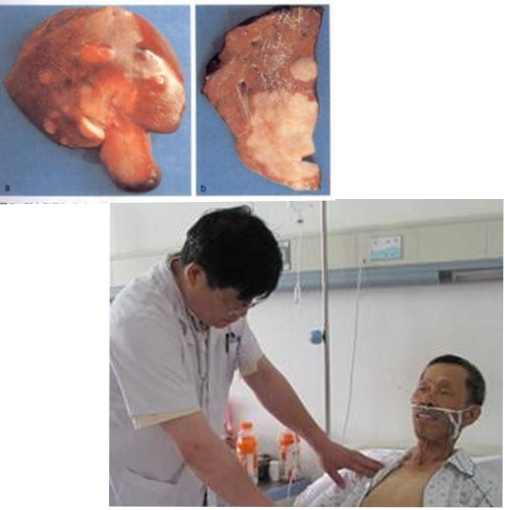

膽管癌圖片

早期肝膽管癌

內膽管癌早期症狀

肝門膽管癌晚期